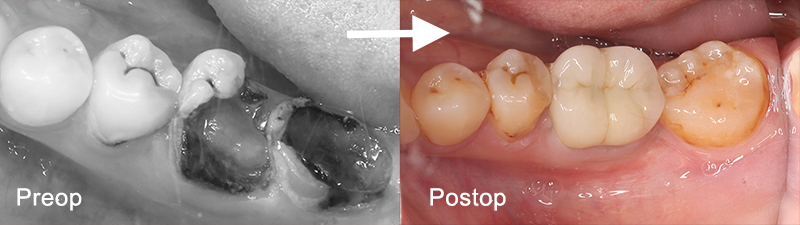

年配者と若者世代では歯科再建治療に対するアプローチはまったく異なる。 生存年数や活動年数が中高年世代と20代の世代では30年以上の実質差があり、長期的な戦略としてはエナメル質の保存、歯髄の保存が最優先し、生体としての自己再生能を維持すべき治療が推奨される。 以下の症例は治療開始時24歳で下顎第一大臼歯は歯冠崩壊が顕著であるも、歯根部はかろうじてカリエス進行から免れるが、第二大臼歯は完全に歯根も腐食して保存不能。

世代が上がれば後方の90度変位した埋伏智歯の移植利用を考えるが歯髄失活は免れないため、困難な矯正であるが萌出間もない大臼歯として今後を託せる生活歯のまま保存する。 矯正用のアンカースクリューと各種装置を智歯に接着させ、移動の各段階で交換しながら抜歯した第二大臼歯部に誘導する。 第一大臼歯は保存治療後ジルコニアセラミック冠で歯冠修復し約7年経過。 治療期間は 2017/12~2019/03

ムシバを放置したため歯冠崩壊顕著の大臼歯

左:治療開始時2017/12 右:健診時2023/07